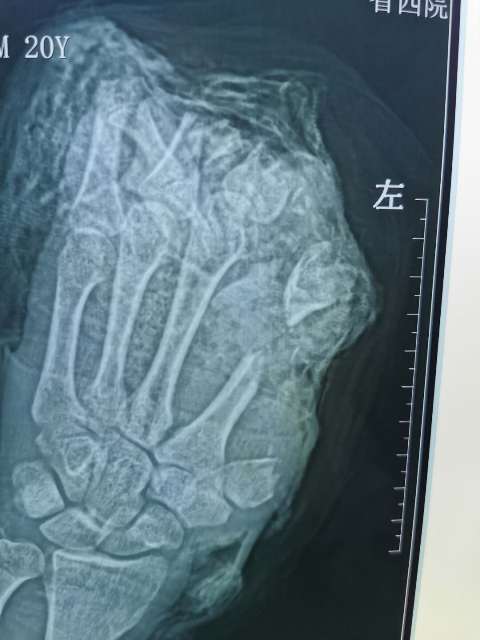

10月6日,20岁的小伙在工厂干活时左手不慎被切割机致左手拇指、示、中、环指完全离断;左小指开放伤伴肌腱神经血管离断;大鱼际皮肤软组织、环指中末节部分缺损、第一掌骨、第二掌骨部分缺损,鲜血直流。被工友慕名紧急送往亚色视频

经过骨二科和手术室医务人员历时10小时,彻底清除污染失活组织及伤口内大量铁屑异物、逐步固定指骨、缝合肌腱,显微下再次清创后吻合离断神经;术中见离断动脉大部分挫伤严重无法吻合就近利用手背侧静脉,移植搭桥吻合缺损动脉完成4指离断一期急诊再植,术后经补液输血,支持,抗感染,抗凝,抗痉挛,扩血管等“三抗一扩”对症治疗。目前患者再植指体成活良好,已经基本度过危险期,保住了患者的四个手指。